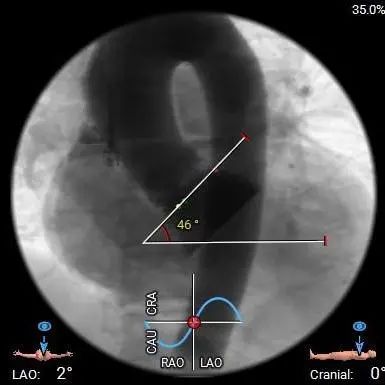

直径20mm TaurusAtlas球囊进行预扩,同时预装TaurusElite AV23瓣膜。瓣环下0-2mm开始定位释放。释放过程中多角度造影,超声辅助定位确定瓣膜最终位置。释放后再次造影确定佐证。

瓣膜定位

瓣膜微释放

释放至工作位

超声明确瓣膜位置

瓣膜释放

超声评估

开始释放

完全释放

术中20mm球囊预扩可见明显腰征,无瓣周漏,左冠充盈速度可。选择TaurusElite  AV23瓣膜送至主动脉弓,输送系统轻松过弓及跨瓣,精准定位无冠窦最低点,利用可回收功能,术中对位置进行适当调整,大大提升了瓣膜精准释放的几率,保证了手术的安全性。

TaurusElite AV23瓣膜经过2次调整之后,第3次释放定位位置接近瓣环,心脏瓣膜团队精确定位,零位释放,瓣膜在术前评估的位置牢牢锚定!整个手术过程连贯如行云流水,团队配合默契,操作细致熟练,主动脉根部造影及即时食道超声提示无瓣周漏,TaurusElite首秀成功!